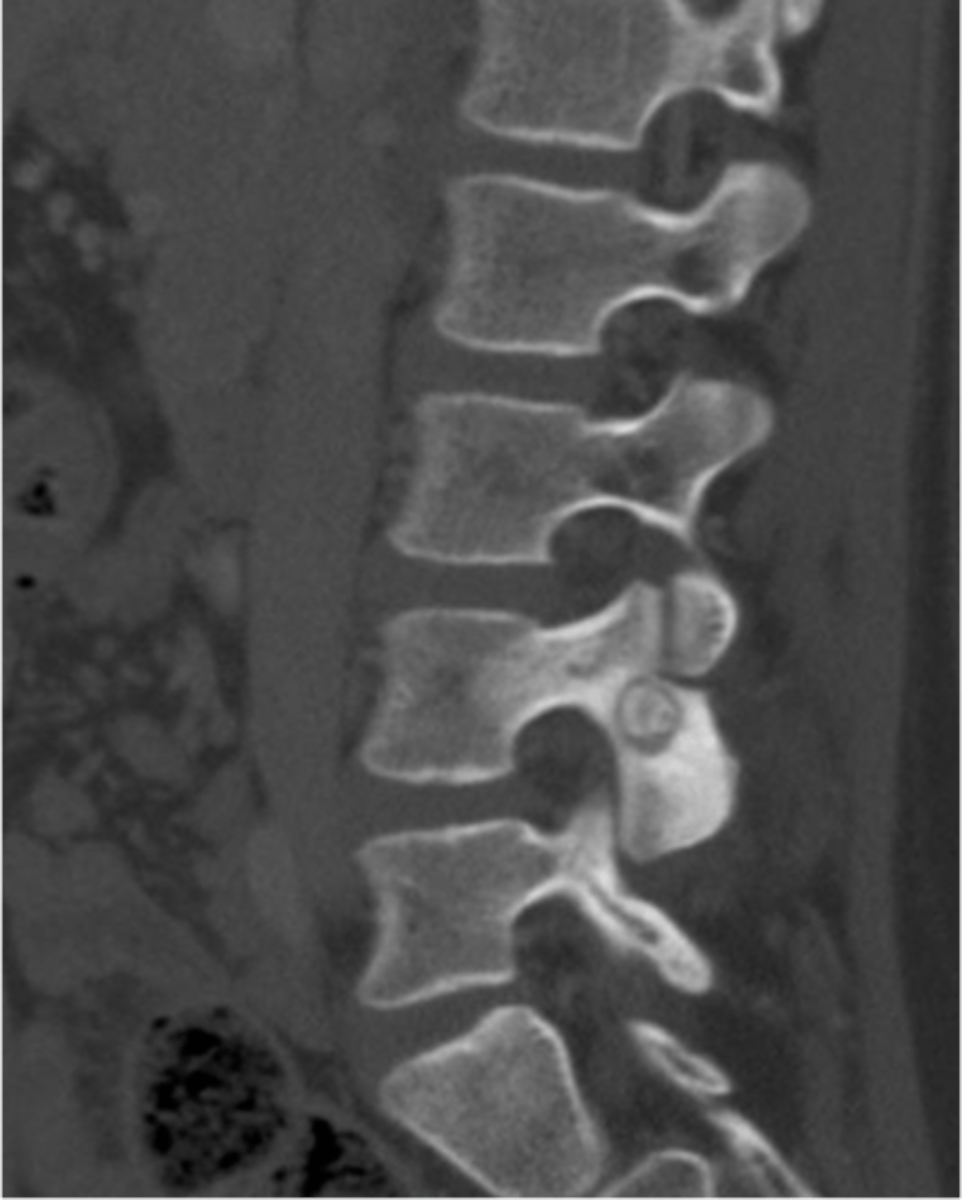

Vertebral hemangioma

- Solitary vascular neoplasm

- Slow growing

<p>- Solitary vascular neoplasm</p><p>- Slow growing</p>

42

New cards

- 2-3% of all spine tumors (radiographs)

- 11% of all spines (autopsy)

- Most common benign tumor of the spine

State the incidence of vertebral hemangioma

- First seen over 40 y.o.

- F>M

- Most asymptomatic

- 75% in spine and skull

- Lower thoracic and upper lumbar

- Vertebral body

• Extension into vertebral arch (10-15%)

State the clinical features of vertebral hemangioma

- Vertical striations (corduroy cloth)

- Expansion (rare) may result in neurologic findings

- Skull ("sand dollar")

- Paravertebral swelling

State the radiographic features of vertebral hemangioma

<p>State the radiographic features of vertebral hemangioma</p>

- Left: Paget Disease

- Middle: Vertebral hemangioma

- Right: Osteoporosis

Complete the DDx for vertebral hemangioma

<p>Complete the DDx for vertebral hemangioma</p>